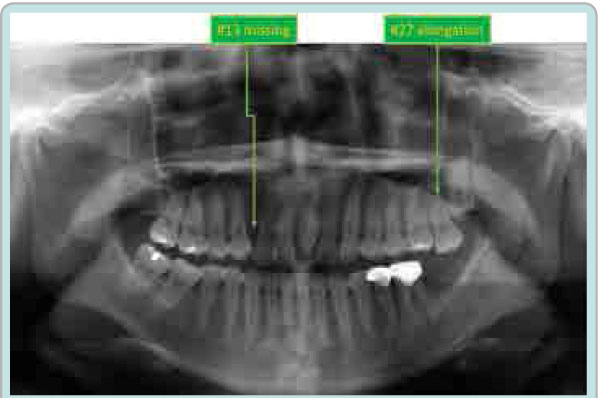

The space analysis showed 8.0 mm of space deficiency in the upper dentition and 1.5 mm space deficiency in the lower dentition. Both upper and lower dental arches were symmetric ovoid shape (Figure 1). Panoramic findings showed #13 missing and #27 elongation (Figure 2). Cephalometric analysis indicated that this patient had a skeletal Class I pattern with an ANB angle of 3.4 ° with a mean mandibular angle. The upper incisor positions showed tendency of mild retroclination measured from U-1 to A-P plane of 5.3mm. The mandibular incisors were retroclined as compared to norms. (Figure 3, Table 1).

Figure 2: Initial Panoramic radiograph